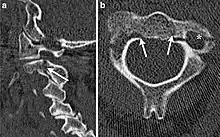

| CT scan of hangman's fracture | |

Hangman's fracture is the colloquial name given to a fracture of both pedicles, or partes interarticulares, of the axis vertebra (C2).[1]

Although a hangman's fracture is unstable, survival from this fracture is relatively common, as the fracture itself tends to expand the spinal canal at the C2 level. It is not unusual for patients to walk in for treatment and have such a fracture discovered on X-rays. Only if the force of the injury is severe enough that the vertebral body of C2 is severely subluxed from C3 does the spinal cord become crushed, usually between the vertebral body of C3 and the posterior elements of C1 and C2.